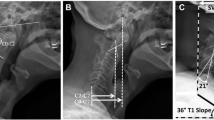

Abnormal neck alignment, or cervical deformity, can be quantified by multiple radiographic techniques. One common measure is the sagittal vertical alignment (SVA) of C2 vertebra relative to C7 (C2–C7 SVA). The SVA is calculated as the horizontal distance from a C2 plumb line to the C7 vertebral body (Fig. 1) [3, 4]. A second measure is the T1 sagittal angle (T1 tilt) [5]. This calculates the angle between a horizontal line and the superior endplate of T1. The T1 tilt is a surrogate for the degree of thoracic kyphosis. Previously, our laboratory reported an ex vivo biomechanical cervical model that can be used to evaluate the biomechanical consequences of cervical neck deformity by modifying these two key variables [6]. The cervical model serves as a platform to evaluate how these components of deformity impact the biomechanics of the cervical spine. We used reconstructed three-dimensional (3D) computed tomography (CT) modeling, to evaluate the impact of deformity on the nerve root foramen.

Cervical sagittal alignment measurements in an asymptomatic patient (a) and a patient with forward head posture (b). C2–C7 SVA is defined as the distance from the posterior superior corner of C7 to a plumb line drawn from the center of the C2 vertebral body. T1 tilt is defined as the angle between a horizontal line and the superior end plate of T1